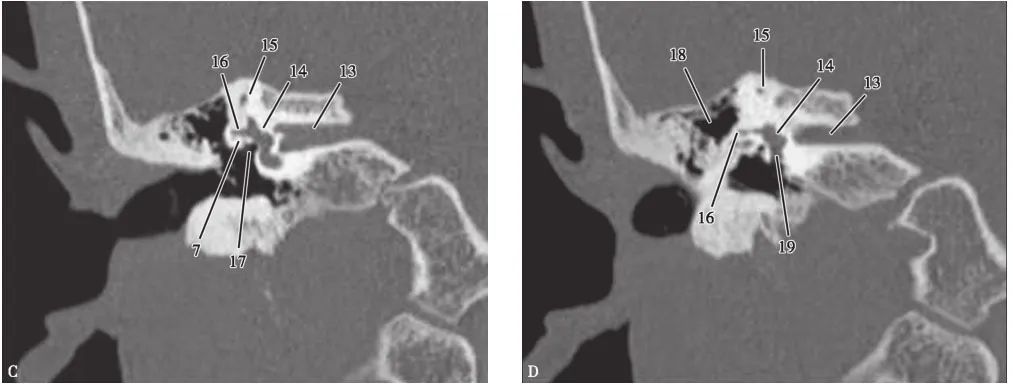

(CT冠状面)

A.岩尖层面;B.耳蜗层面;C.前庭窗层面;D.蜗窗层面;E.总骨脚层面;F.面神经管乳突段层面1.颈动脉管;2.鼓膜张肌;3.咽鼓管;4.颞颌关节;5.耳蜗;6.面神经管迷路段;7.面神经管鼓室段;8.锤骨头;9.盾板;10.锤骨颈;11.锤骨柄;12.鼓膜张肌;13.内耳道;14.前庭;15.上骨半规管;16.外骨半规管;17.前庭窗;18.乳突窦入口;19.圆窗;20.耳蜗导水管;21.总骨脚;22.弓形下窝;23.颈静脉球;24.乙状窦;25.后骨半规管;26.面神经管乳突段